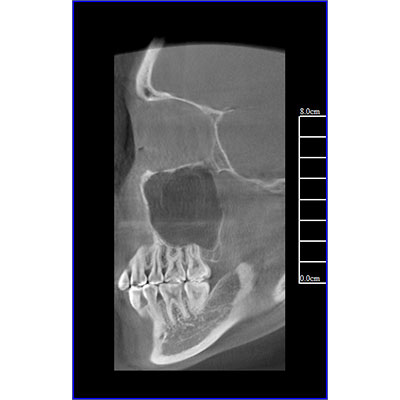

采用高端平板探测器,分辨率高、图像质量优。

专有三维重建算法,可提供任意位置高清断层影像。

可同时观察轴向面、冠状面和矢状面图像,方便临床诊断。